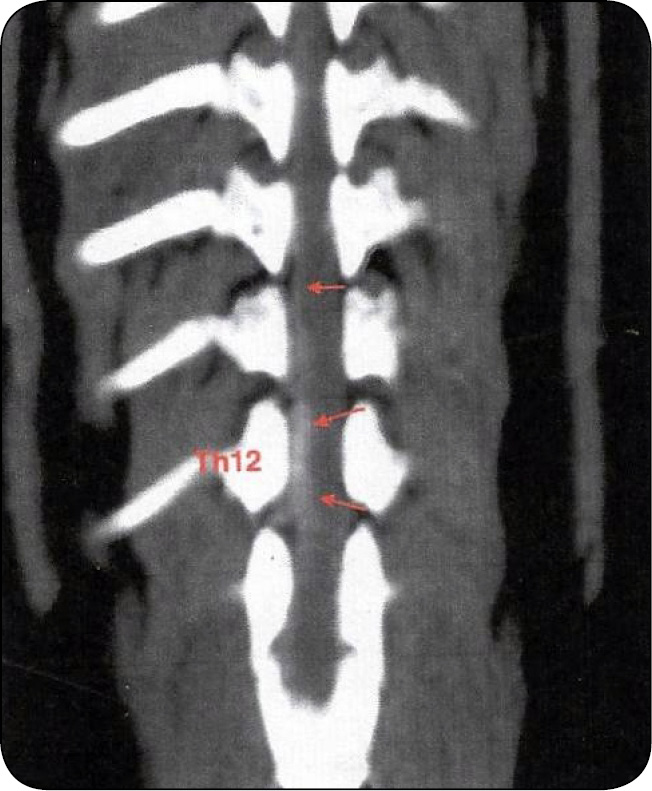

Drugi epizod dyskopatii miał miejsce 4.09.2023 r., zgodnie z wywiadem klinicznym przez dwa dni postępował niedowład kończyn miednicznych, aż zwierzę przestało chodzić. Właściciel zgłaszał również, że pies w pewnym momencie przestał wykazywać silne oznaki bolesności. Oddaje mocz samodzielnie, bezwiednie, kał również. W badaniu klinicznym, które wykonywał lekarz weterynarii, stwierdzono: brak korektury kończyn miednicznych, brak czucia bólu głębokiego w kończynach miednicznych, wzmożone napięcie w ww. kończynach, odruch zginaczy obecny, odruch rzepkowy wzmożony, odruch mięśniowo-skórny nieobecny do wysokości ± Th13. Wykonano wówczas badanie tomograficzne odcinka piersiowo-lędźwiowego kręgosłupa – natywne oraz po podaniu dożylnego środka kontrastowego. Wyniki przedstawiały się następująco: stan po dokanałowej, prawostronnej ekstruzji jądra miażdżystego krążka międzykręgowego Th12/13 (ryc. 4).

Masa dysku wykazuje densyjność tkanek miękkich – rozciąga się na terenie kanału kręgowego od poziomu przestrzeni międzykręgowej na całej długości trzonu Th12, po stronie prawej, gdzie masy osiągają około 50% przekroju kanału kręgowego – doprowadzając do ucisku rdzenia kręgowego umiarkowanego stopnia. Dodatkowo w badaniu widoczne jest wzmocnienie pokontrastowe w postaci wąskiego pasma, rozciągającego się w kierunku doczaszkowym, do poziomu Th6, widoczne po stronie prawej, podejrzewa się obecność krwiaka po ekstruzji. Stan po prawostronnej hemilaminektomii Th13/L1 – na dnie kanału ww. okolicy widoczna nieznaczna ilość mas dyskowych, osiągających około 25% przekroju kanału kręgowego, możliwy ucisk łagodnego stopnia. Dodatkowo centralna protruzja krążka międzykregowego [...]